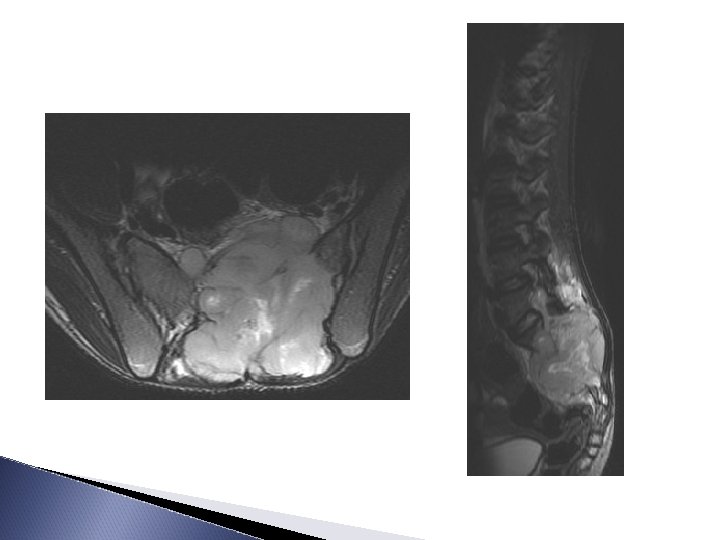

15 ans, Tm d’Ewing sacrée avec envahissement endocanalairet skip métastase du fémur TDM+C T 1 -c T 2 T 1 +c T 2 FAT-SAT